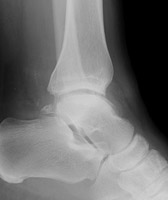

B | Mortise radiograph of the ankle. There is a radiolucent lesion at the lateral aspect of the talus, corresponding to the site of osteochondritis dissicans. |